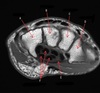

30

What is letter A?

CLAVICLE

31

What is letter B?

AC JOINT

32

What is letter C?

SUPRASPINATUS TENDON

33

What is letter D?

BICEPS TENDON

34

35

STERNOCLAVICULAR JOINT

36

STERNAL NOTCH

37

VERTEBRAL BODY

38

What is letter E?

RT LUNG

39

What is letter F?

SCAPULA

40

HUMERAL HEAD

41

ACROMION

42

43

44

STERNUM

45

CORACOID PROCESS